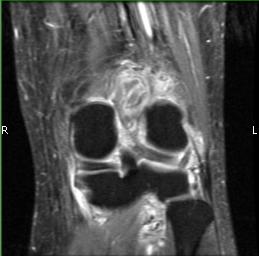

MRI (Fig. 1-10)

- Periarticular or synovial nodular mass with varying degrees of bone erosion.

- Nodular lesion with areas of hemosiderin (low signal on all sequences) and hemorrhage.

- On fat suppress images the tumor is high signal and hemosiderine cannot be seen.

- Joint effusions and bony erosions are well demonstrated. As with CT, contrast enhancement is typical.

Fig. 1-10: Magnetic Resonance of a PVNS of the knee shows a synovial mass with minimal bone erosion of the medial articular plate. On T1W and T2W images shows a tumor with low intensity areas (hemosiderin) and hemorrhage. Joint effusion is well demonstrated. Post contrast images demonstrate an irregular pattern of enhancement.